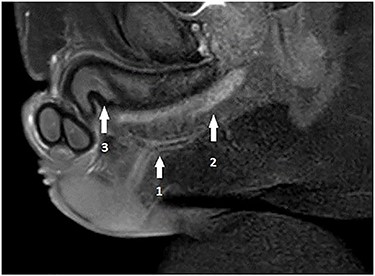

A 32-year-old male, with no previous major health problems, presented to our department complaining of scrotal fistula leakage of purulent fluid. The condition had started 6 months before. The physical examination revealed a productive scrotal fistula. He denied any dysuria or burning micturition or pyuria. His initial laboratory reports and urinalysis were unremarkable. A scrotal ultrasound revealed a thickening of the scrotal skin with no collection. Voiding cystourethrography was normal (no strictures). Magnetic resonance imaging (MRI) at that time showed a horizontal one-eyed fistula on the medial ligne above the corpus spongiosum, ending vertical with no collection (Fig. 2). The patient underwent an operative procedure, via a scrotal approach, the fistula was injected with methylene blue and a blind channel was excised from the surrounding tissues along his entire length. This channel measured 10.5 cm (Fig. 3). The diagnosis of urethral duplication had not been established at that time, but only on the pathology report.

Pelvis MRI: horizontal one-eyed fistula (1) on the medial ligne above the corpus spongiosum (2), ending vertically with no collection and (3) corpus cavernosum.